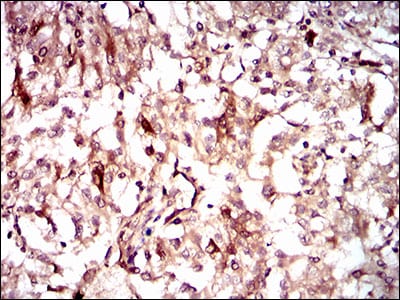

Immunohistochemical analysis of paraffin-embedded human renal cancer tissues using GUCY1A3 mouse mAb with DAB staining.